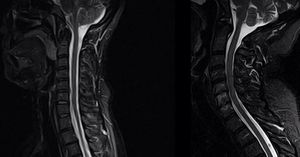

STIR images usually suffer from truncation (Gibbs/ringing) artifacts in spine (left image). These artifacts are particularly problematic in spinal imaging, in which they may artifactually widen or narrow the cord or mimic a syrinx. Optimized protocol (right image) provides much better spatial resolution and is free from this kind of artifacts (look at the medulla).